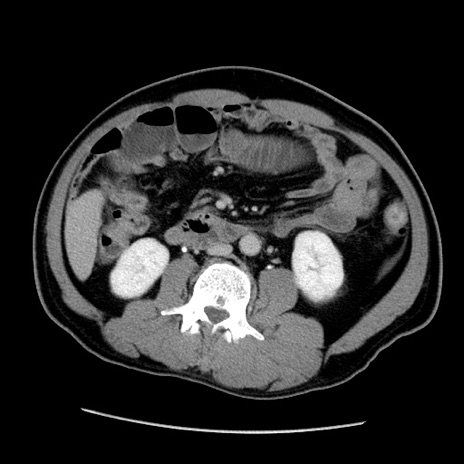

症例22(横断像)

【症例】50歳代男性

【主訴】腹痛

【現病歴】AVMからの被殻出血のため回復期リハ病棟入院中。 本日午後3時頃急に下腹部痛が出現した。

【既往歴】AVM、被殻出血、虫垂炎、高血圧

【身体所見】意識晴明、左半身不全麻痺、会話の理解は良好、36.5°C、腹部:膨隆、全体に板状硬、下腹部正中に圧痛点あり、反跳痛-、筋性防御不明、右下腹部にope scar

【データ】WBC 9400、CRP 0.06